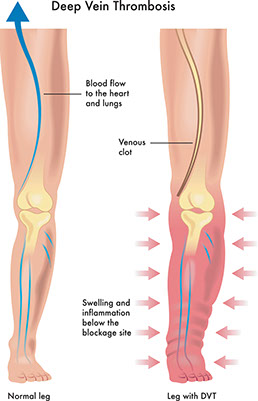

Deep-vein thrombosis (DVT) with or without a blood clot to the lung

Signs & Symptoms

Pain, redness (may have shades of red, purple, and blue), or swelling in one ankle or leg. May be followed by severe shortness of breath that came on all of a sudden. May include coughing up blood or pink-frothy sputum. Chest pain.

What to Do

Get medical care fast!